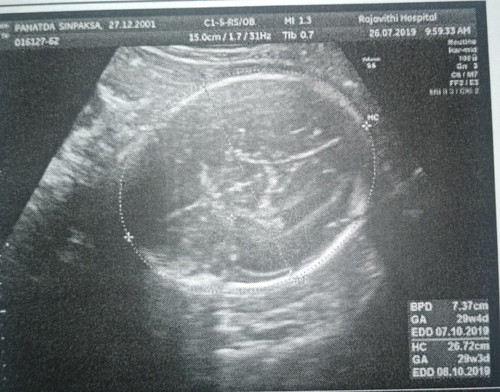

เห็นชัดแค่รูปศีรษะ ส่วนเพศ แม่น่าจะถามหมอนะคะ ตัวน้องโตแล้ว น่าจะชัดแล้ว ถ้าไม่หนีบไว้ หมอน่าจะบอกได้

นั่นมันกระโหลกศีรษะน้องค่ะคุณแม่ ต้องดูท่าก้นนะคะถึงจะรู้ ในรูปนี้ผู้ชาย

รูปไม่ได้เห็นระหว่างขาเลยนะคะ มีแต่รูปกะโหลกศีรษะน้อง รูปกระดูกไขสันหลัง

เอิ่ม รูปกระโหลกศรีษะ บอกเพศไม่ได้ค่า ทำไมไม่ถามหมอละคะ แล้วจะรู้ไหมนิ

อันนี้มันรูปกระโหลกศีระลูกค่ะ นี่ไมีฟังหมอพูดหมอบอกเลยหรอคะ

นี่รูปหัวกระโหลกศรีษะน้องค่ะ ต้องดูรูปหว่างขานะคะถึงจะดูออก